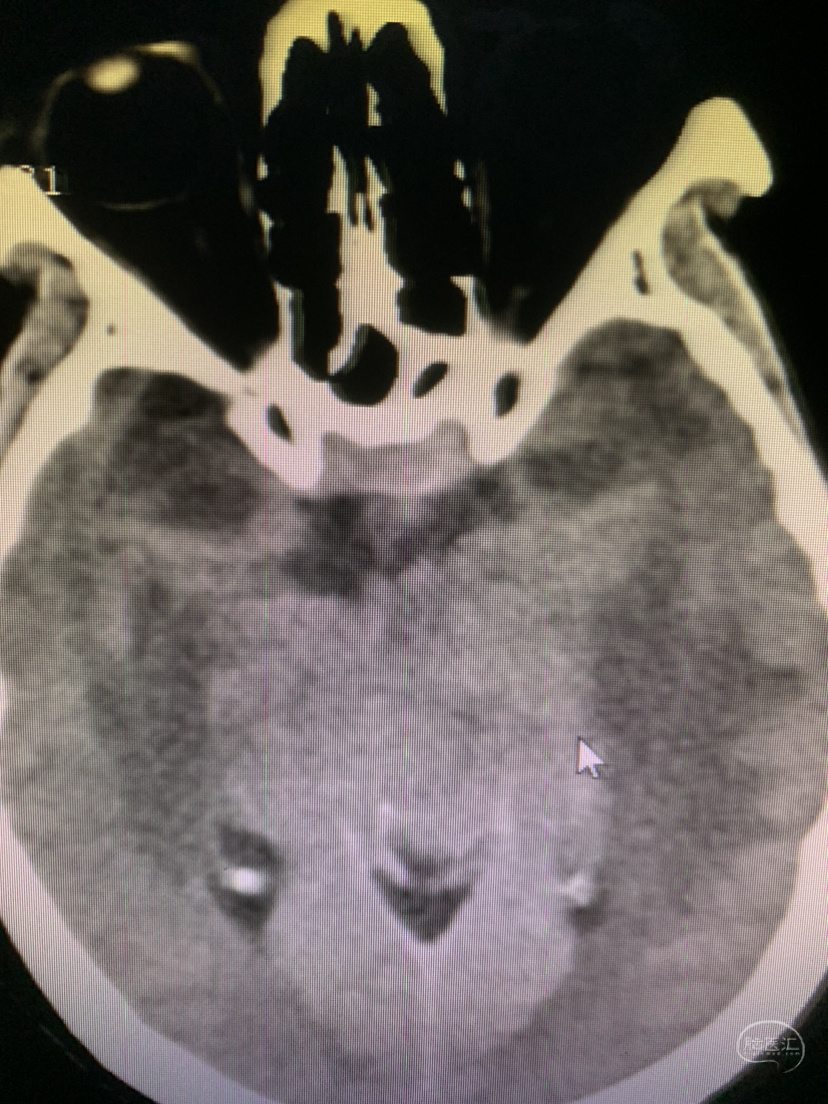

术前CT

术前CT